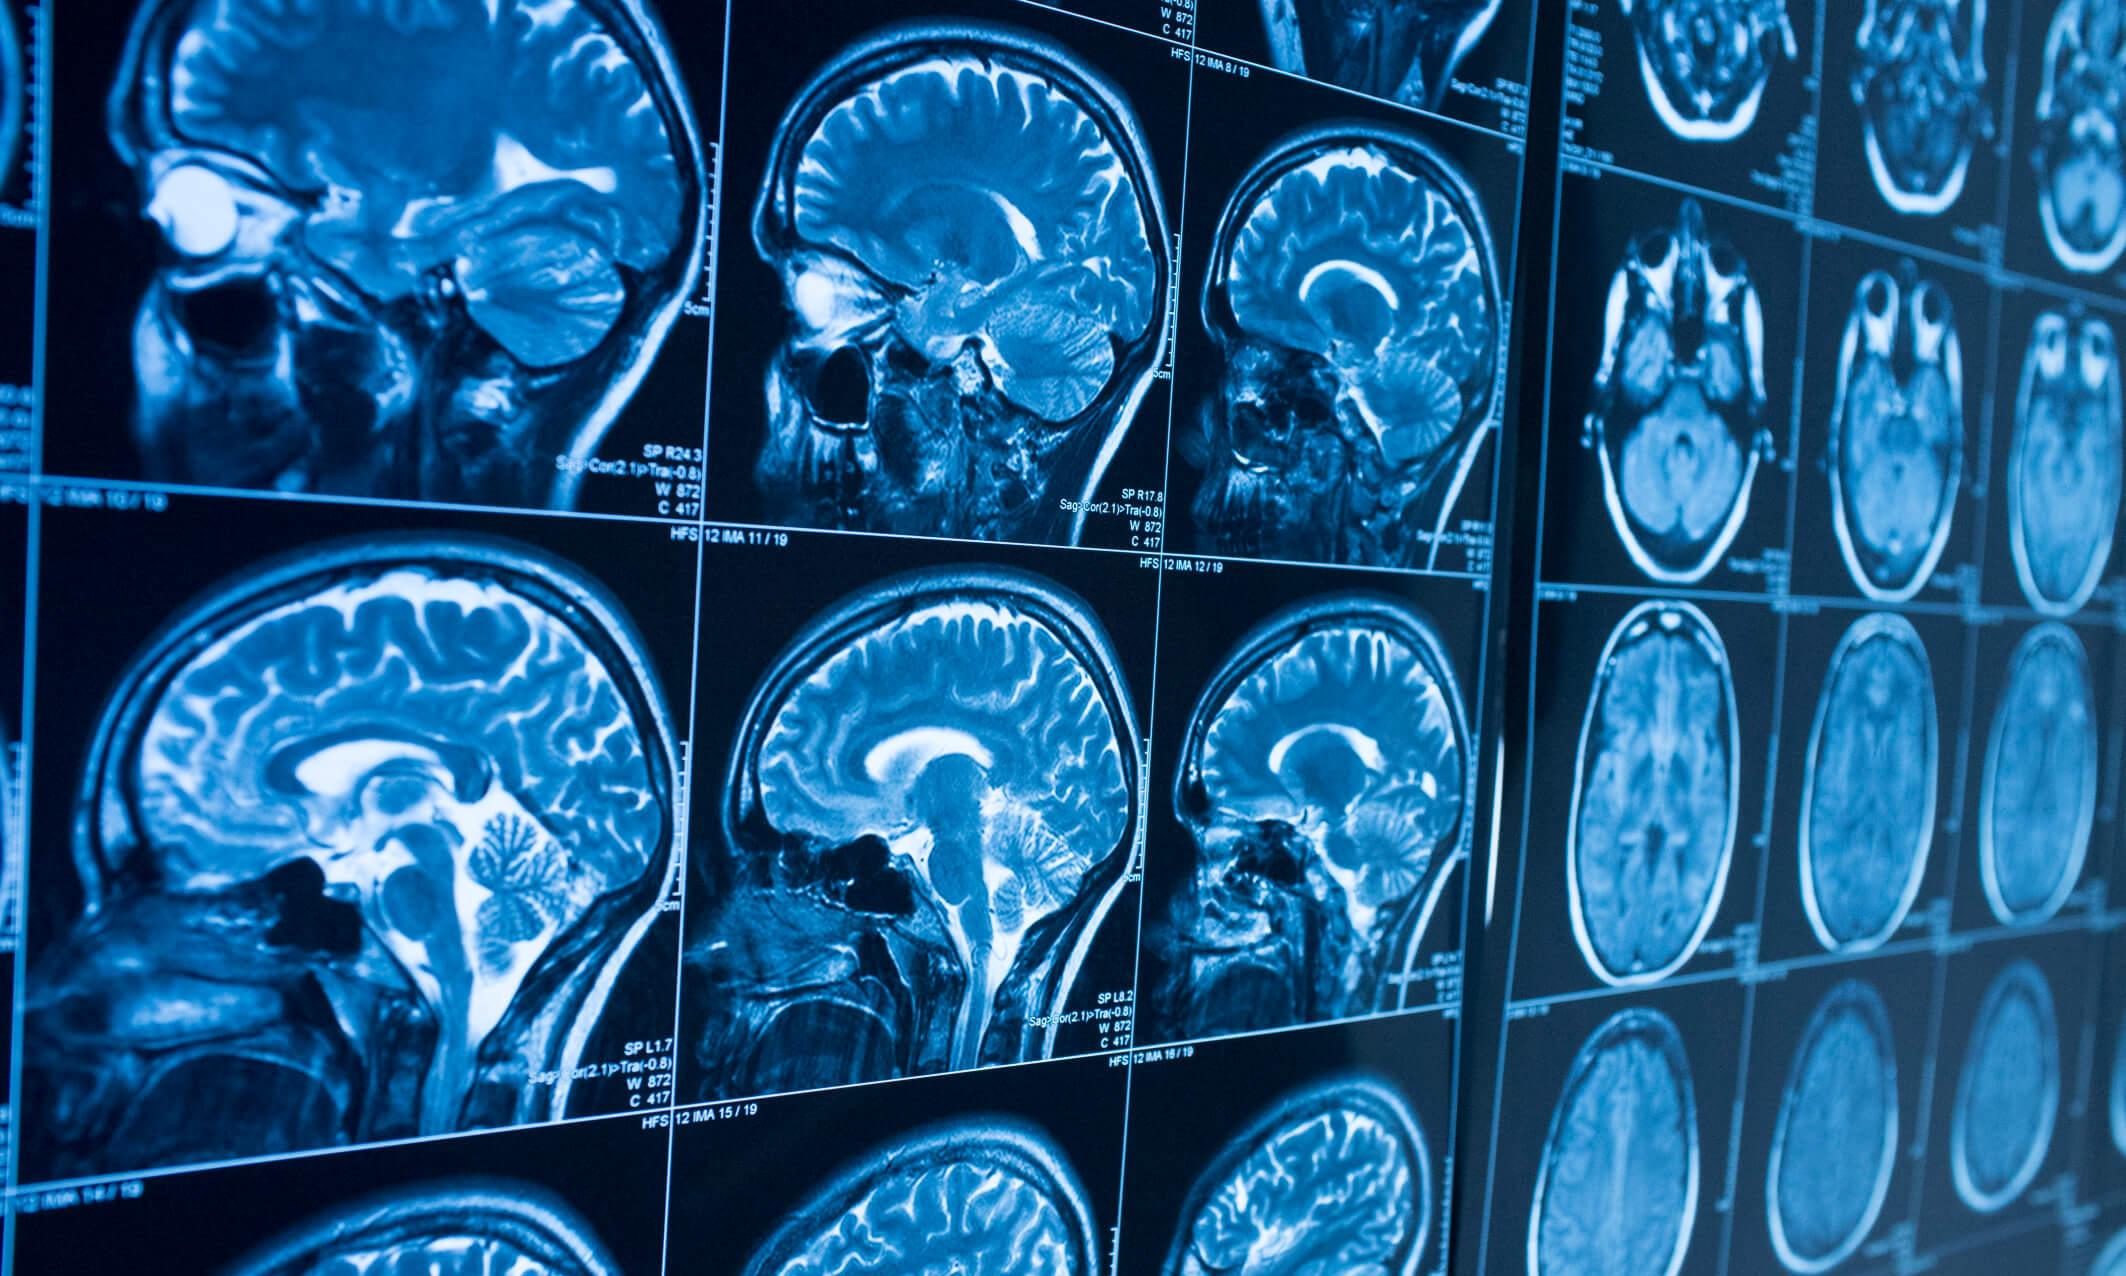

In their study, the researchers utilized two datasets and lesion network mapping to determine if lesions causing acquired stuttering correspond to a common brain network. They also used a third dataset to assess the relevance of this lesion-based network to developmental stuttering.

Through analysis of each dataset, the team identified a common stuttering network, specifically in the left putamen, which is involved in lip and face movements, as well as the timing and sequencing of speech.